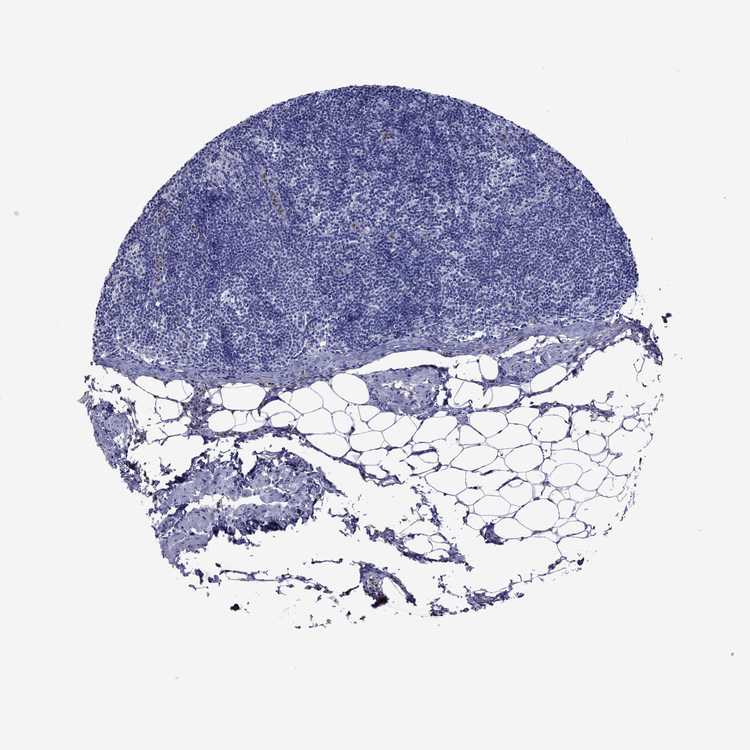

TISSUE PRIMARY DATA LYMPH NODE Show tissue menu

Lymph node

LYMPH NODE - Expression summary

LYMPH NODE - Antibody stainingi

Antibody staining in the annotated cell types in the current human tissue is reported as not detected, low, medium, or high, based on conventional immunohistochemistry profiling in selected tissues. This score is based on the combination of the staining intensity and fraction of stained cells.

Each image is clickable and will lead to virtual microscopy that enables deeper exploration of all samples and also displays staining intensity scores, fraction scores and subcellular localization as well as patient and tissue information for each sample.

Antibody HPA073125Antibody CAB016255

Germinal center cells Not detectedNot detected

Non-germinal center cells Not detectedNot detected